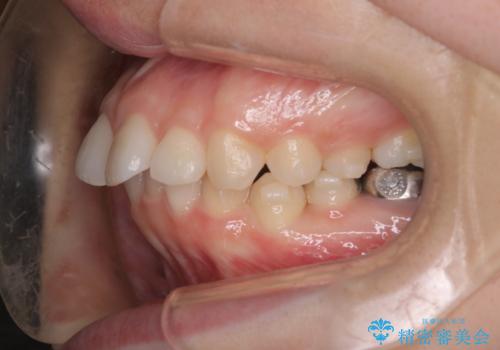

【インビザライン】前歯を引っ込めたい

- 前歯が出ていることを主訴に来院された患者様です。

抜歯を希望されなかっため、臼歯部の遠心移動やIPRを行い配列を行っています。

抜歯をしていない矯正となるため、口元に大きな変化は認められません。